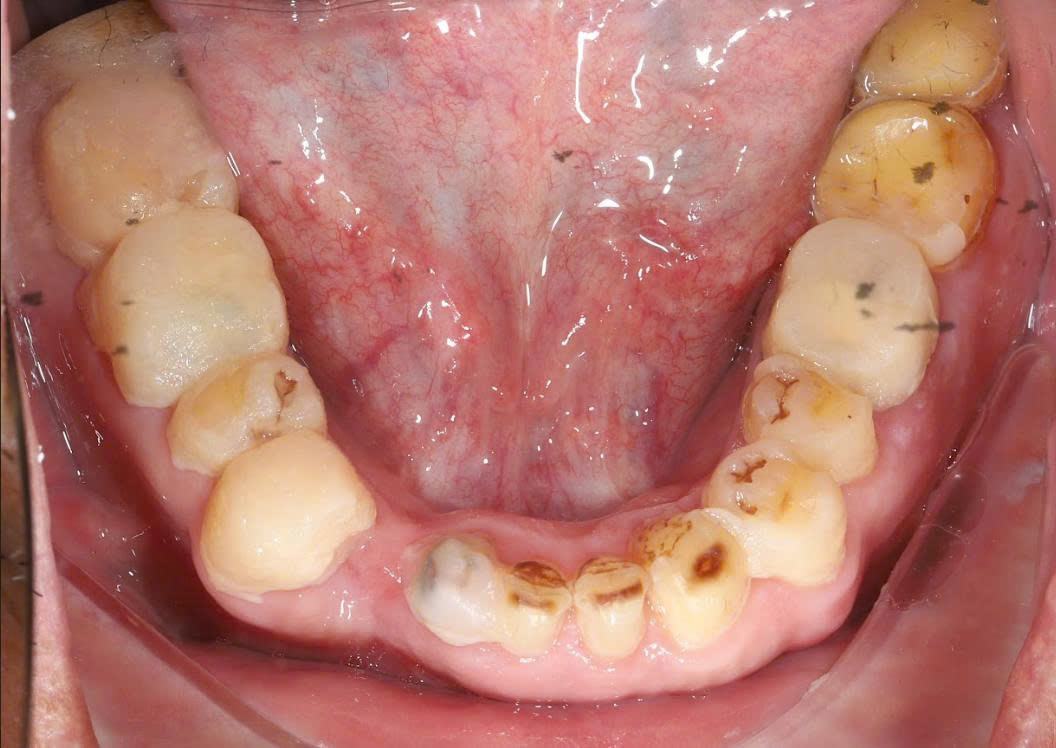

3.1 Khám trong miệng

-

Hầu hết các răng hai hàm đã bị mài nhỏ quá mức

Răng số 8 (răng khôn) bị mài và bọc sứ – hoàn toàn sai chỉ định

Viền lợi không đều, có dấu hiệu viêm quanh răng

Bệnh nhân phản ánh đau nhức âm ỉ kéo dài

3.2 Chẩn đoán hình ảnh

Phim X-quang cho thấy:

Răng số 8 không còn giá trị chức năng, là nguồn gây đau

Một số răng trụ bị mài sát buồng tủy

Khớp cắn mất cân đối do phục hình không chuẩn